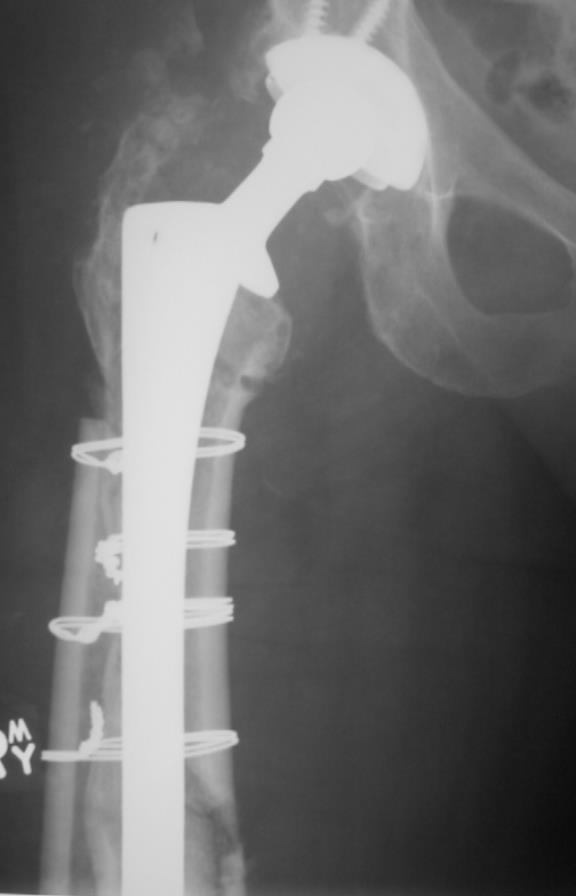

일상생활을 하다가 부러진 경우에도 똑같은 Vancouver Classification 을 사용합니다. 수술중과 큰 차이는 위치에 따라 골절을 나뉘고 B만 구체적으로 나누고 나머지는 그냥 A,C로 골절을 나뉩니다. STEM 이 헐거운 경우 B2, STEM 바로 아래는 B1, 삽입물 주변의 골절 또는 뼈가 부족한경우 B3로 이해하면 됩니다.